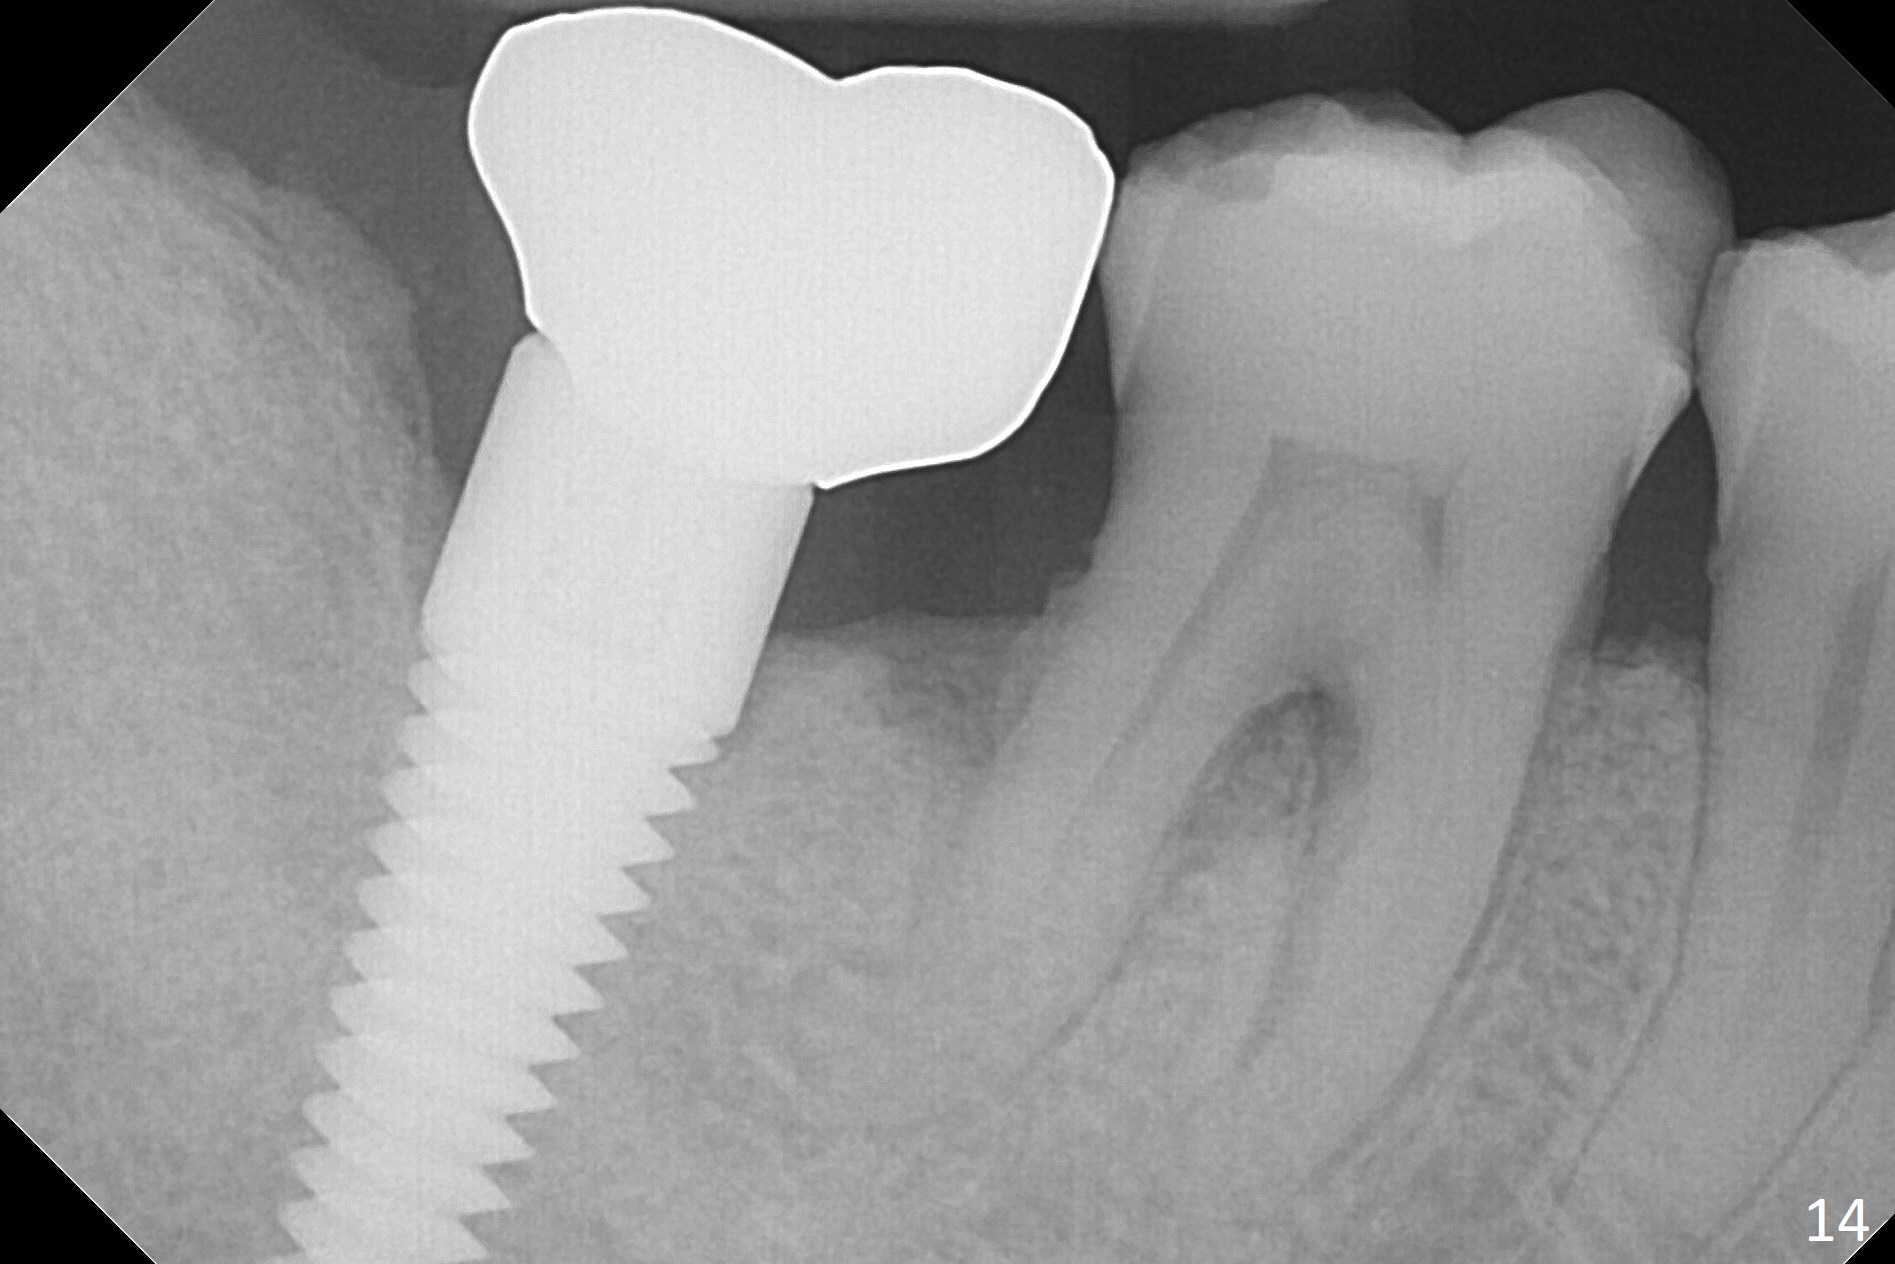

A 50-year-old man, a smoker, presents to clinic with pain of the tooth #15 with apparently occlusal trauma (Fig.1). Two years and three months after #15 extraction, he returns for #31 extraction (Fig.2) and socket preservation (Fig.3). The socket depth is 17 mm along the long axis of the socket 2.5 months post extraction (Fig.4, gingival level). Initial osteotomy is created in the mesial slope of the socket for 14 mm (Fig.5). After sequential osteotomy, a 6x17 mm tap is seated shallower (Fig.6) than the 2 mm drill (Fig.5). Following further osteotomy, a 7x14 mm implant is seated incompletely (Fig.7), which was not found intraop. The implant becomes loose with purulent discharge 19 days postop. The patient returns for 2nd placement 2 months post implant removal (Fig.8). Osteotomy is created probably in the mesial slope with 17 mm (bone level, Fig.9). After insertion of 5 (Fig.10) and 6 (Fig.11) x20 mm taps (tissue level), a 6x20 mm tissue-level implant is placed with clearance from the Inferior Alveolar Canal (Fig.12 yellow dashed line). The implant is restored 8.5 months postop (Fig.13) without bonding 5 mm 0 degree unipost. The crown dislodges 4 months post permanent cementation. Still the patient complains of small crown without occlusal contact. Impression is taken for a new normal-sized crown. The new crown becomes loose 1 year 9 months post cementation (Fig.14). The teeth #14 and 15 remain unrestored.